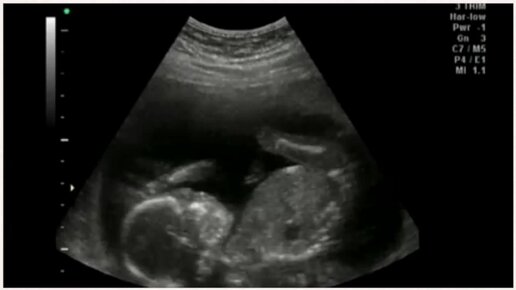

УЗИ на 17 неделе беременности